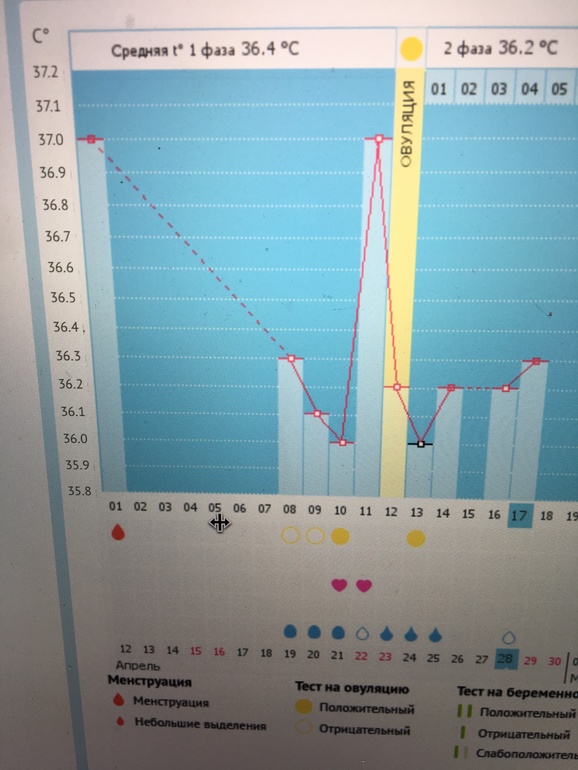

бт по сколько после овации поднимается ежедневно ?

Девочки посмотрите мой график ну что за дурдом ? овуляция по узи подтверждено 27 числа

Можете поставить "не учитывать" на 11 дц. Тогда на графике ещё вообще не будет отмечена овуляция. Почему нет сердечек в районе 27 числа? Или просто не ставили?

и первую фазу он не правильно установил у меня Бт 36 или 35,9

Программа ставит среднюю температуру за фазу. Она у вас 36,4. Почему не правильно?

а потому что 37 первая я не мерила а просто написала

Тогда убирайте и все. Искажаете всю картину тогда. Здесь же ещё важна разница температур

А почему вы именно так поставили О. Она могла и 26 быть или 25. И каждый день измеряйте, должна подняться

А почему о поставили не на 27 число тогда а раньше?

вроде на 27е ой короче что то вообще не получается разобраться

Ну вот. Уже лучше. Теперь температура должна повышаться.

вот поменяла вроде

ну вот так правильнее и то мне кажется, что она была 24-25, для узи как раз это "только была", но может и 27, это уже не так важно, должна подняться ваша БТ) ждите, удачи)